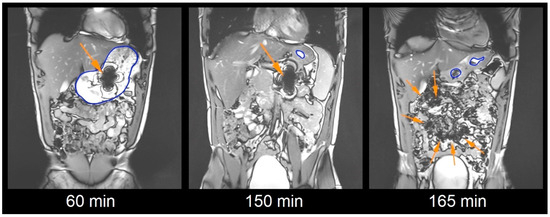

Ready-to-fill enteric hard capsule shells are an evolving field of oral drug and nutraceutical products. Lonza Capsugel® Enprotect® capsules were recently proven to provide reliable release in the small intestine after fasted intake, but robustness against postprandial intake needed to be [...] Read more.

Ready-to-fill enteric hard capsule shells are an evolving field of oral drug and nutraceutical products. Lonza Capsugel® Enprotect® capsules were recently proven to provide reliable release in the small intestine after fasted intake, but robustness against postprandial intake needed to be proven. In this study, the capsules were administered to 16 healthy young subjects after intake of a light meal. The Enprotect® capsules were labelled with 5 mg black iron oxide and 25 mg 13C3-caffeine. Magnetic Resonance Imaging was used to identify the localization and visual dispersion of the capsule filling. The salivary appearance of caffeine was considered a second independent and sensitive marker for the initial release. Whereas the fasted gastric residence time of the capsules amounted to 43 ± 32 min, it was increased to 158 ± 36 min after postprandial intake. Therefore, the mean dispersion time according to MRI and the mean caffeine appearance time were increased to 196 ± 37 min and 189 ± 37 min, respectively. But, similar to fasted administration, no capsule disintegration or leakage was observed in the stomach and 38% of the capsules disintegrated in the jejunum and 62% in the ileum. The mean dispersion time after gastric emptying and the mean caffeine appearance time after gastric emptying amounted to 38 ± 21 min and 31 ± 17 min, respectively. Both did not relevantly change compared to the fasted intake. Only the absolute dispersion time and caffeine appearance were prolonged due to the increased gastric residence and no relevant influence of the light meal was observed on the disintegration or release behavior of Enprotect® capsules after gastric emptying. The capsules also showed robust enteric properties after postprandial administration. Full article